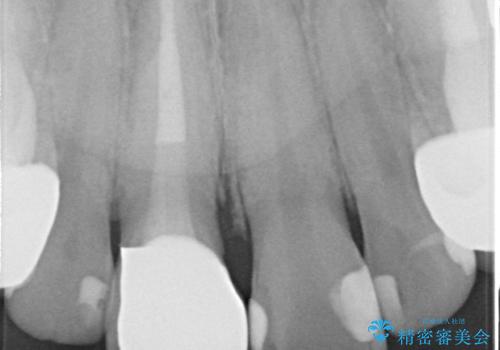

- 右上1の前歯の見た目が気になるので被せ物をやり替えたいといらっしゃった方の症例です。

再根管治療終了後、オールセラミッククラウン(スペシャル)によって隣在歯に合わせた補綴を行いました。